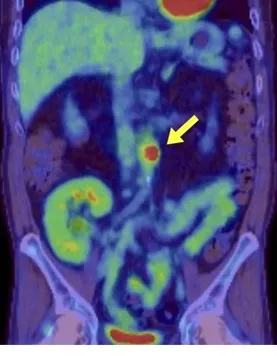

Os achados da TC sem contraste revelaram rins aumentados de tamanho, múltiplos cistos renais e nefrocalcinose (Figura 1).

Os achados tomográficos com contraste mostraram um aspecto de "buquê de flores" na fase excretora (Figura 2).

A síndrome de Beckwith-Wiedemann é uma das causas do rim espongiomedular, que se apresenta comachados específicos na tomografia computadorizada, incluindo nefrocalcinose medular, dilatação cística e um padrão de estrias semelhantes a buquês de flores nas papilas renais.